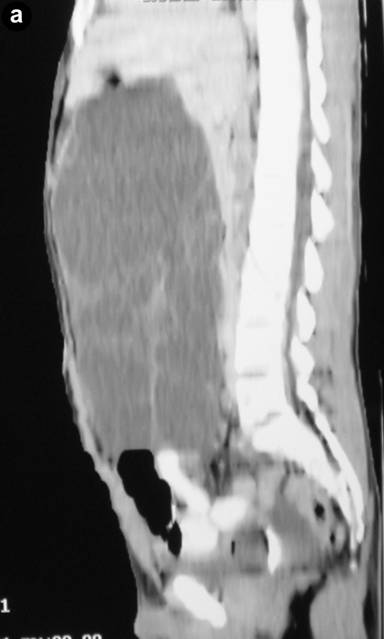

Clinical examination revealed abdominal swelling with generalized tenderness occupying the whole abdomen and almost reaching up to the pelvis. Blood investigation revealed polymorphonuclear leukocytosis (total leukocyte count 12,600 mm-3, reference range: 4,000-11,000 mm-3; polymorphs 91%, reference range: 40-75%). The serum amylase level was 297 U/L (reference range: 20-85 U/L). Liver function tests and CA 19-9 levels were normal. An ultrasound carried out outside our hospital found a large septate cystic collection in front of the pancreas and reported as acute pancreatitis with fluid collection. A CT scan revealed a large multiseptate cystic lesion (23.2x11.7x26.2 cm) anterior to the pancreas reaching up to the pelvis and displacing the gut loops behind and downwards (Figures 1 and 2). We decided to perform a laparotomy with a presumptive diagnosis of cystic neoplasm of the pancreas.

Figure 2. CECT sagittal (a.) and coronal (b.) scan of the abdomen. |